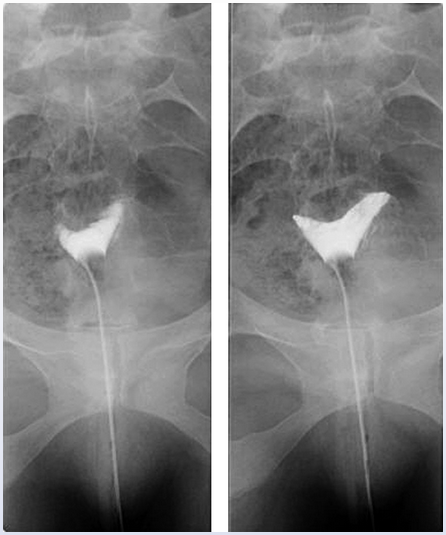

difficulty conceiving.

female factor infertility - has hx of PID, there is no contrast in the tubes, theyre likely scarred